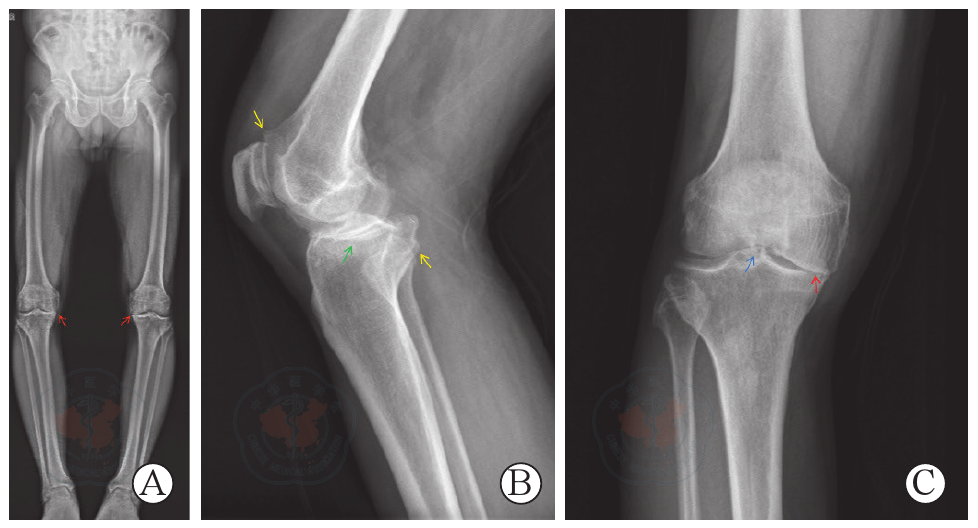

Wu J, Li Y, Zhang X, et al. Assessment of blood flow around the knee joint in patients with knee osteoarthritis by color Doppler ultrasound[J/OL]. Eur J Radiol, 2023, 166: 111005. DOI: 10.1016/j.ejrad.2023.111005.

|